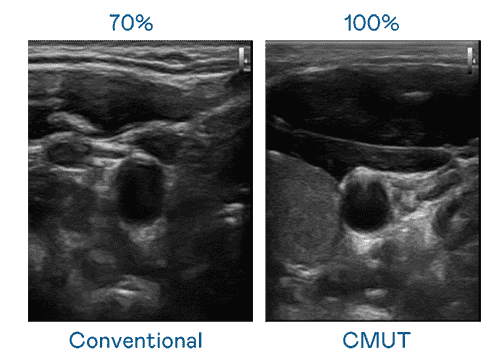

CMUT 技术是一种用电容式微机电元件来产生超音波讯号的技术。。与传统 PZT 压电式技术相比,,,,CMUT 频宽增加 30%,,更宽频的超音波讯号让影像解析度大幅提升,,,是实现高影像品质医疗超音波扫描、、促进精准医疗发展的关键技术。。。

大频宽带来超清晰影像

超音波影像的解析度高低,,,,首先取决于探头能发出的讯号频宽。。。尊时凯龙 CMUT 可提供高清晰的超音波讯号,,,,提供高频宽、、高灵敏度、、、、影像纹理细节更高的超音波影像,,,协助医护人员缩短影像判读时间及利用精准的医疗影像进行诊断。。